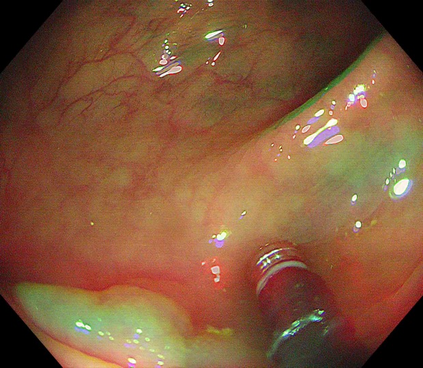

Polyps are early cancer indicators, so assessing occurrences of polyps and their removal is critical. They are observed through a colonoscopy screening procedure that generates a stream of video frames. Segmenting polyps in their natural video screening procedure has several challenges, such as the co-existence of imaging artefacts, motion blur, and floating debris. Most existing polyp segmentation algorithms are developed on curated still image datasets that do not represent real-world colonoscopy. Their performance often degrades on video data. We propose a video polyp segmentation method that performs self-supervised learning as an auxiliary task and a spatial-temporal self-attention mechanism for improved representation learning. Our end-to-end configuration and joint optimisation of losses enable the network to learn more discriminative contextual features in videos. Our experimental results demonstrate an improvement with respect to several state-of-the-art (SOTA) methods. Our ablation study also confirms that the choice of the proposed joint end-to-end training improves network accuracy by over 3% and nearly 10% on both the Dice similarity coefficient and intersection-over-union compared to the recently proposed method PNS+ and Polyp-PVT, respectively. Results on previously unseen video data indicate that the proposed method generalises.